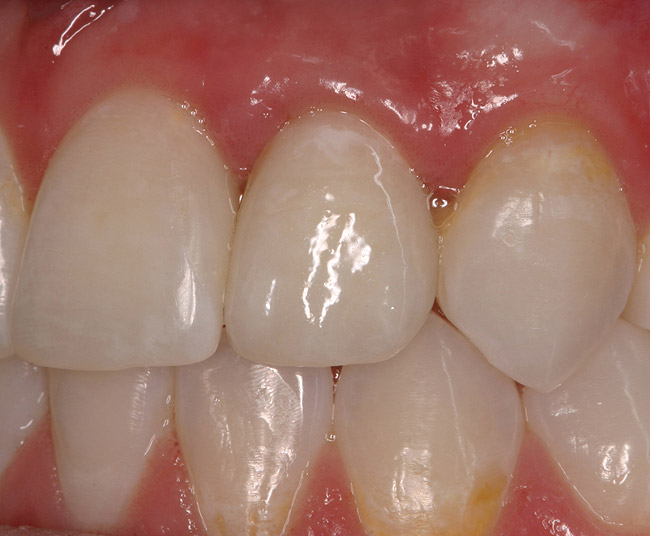

Figure 6a  Upper right central incisor, history of trauma, existing RCT and restoration unsatisfactory.

Figure 6a

Figure 6b  Upper right central incisor, history of trauma, existing RCT and restoration unsatisfactory.

Figure 6b

Figure 6c  Upper right central incisor, history of trauma, existing RCT and restoration unsatisfactory.

Figure 6c